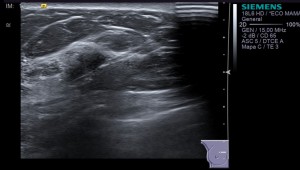

HALLAZGOS ECOGRÁFICOS